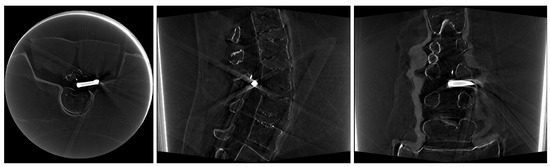

2.4. Image Data

3. Results